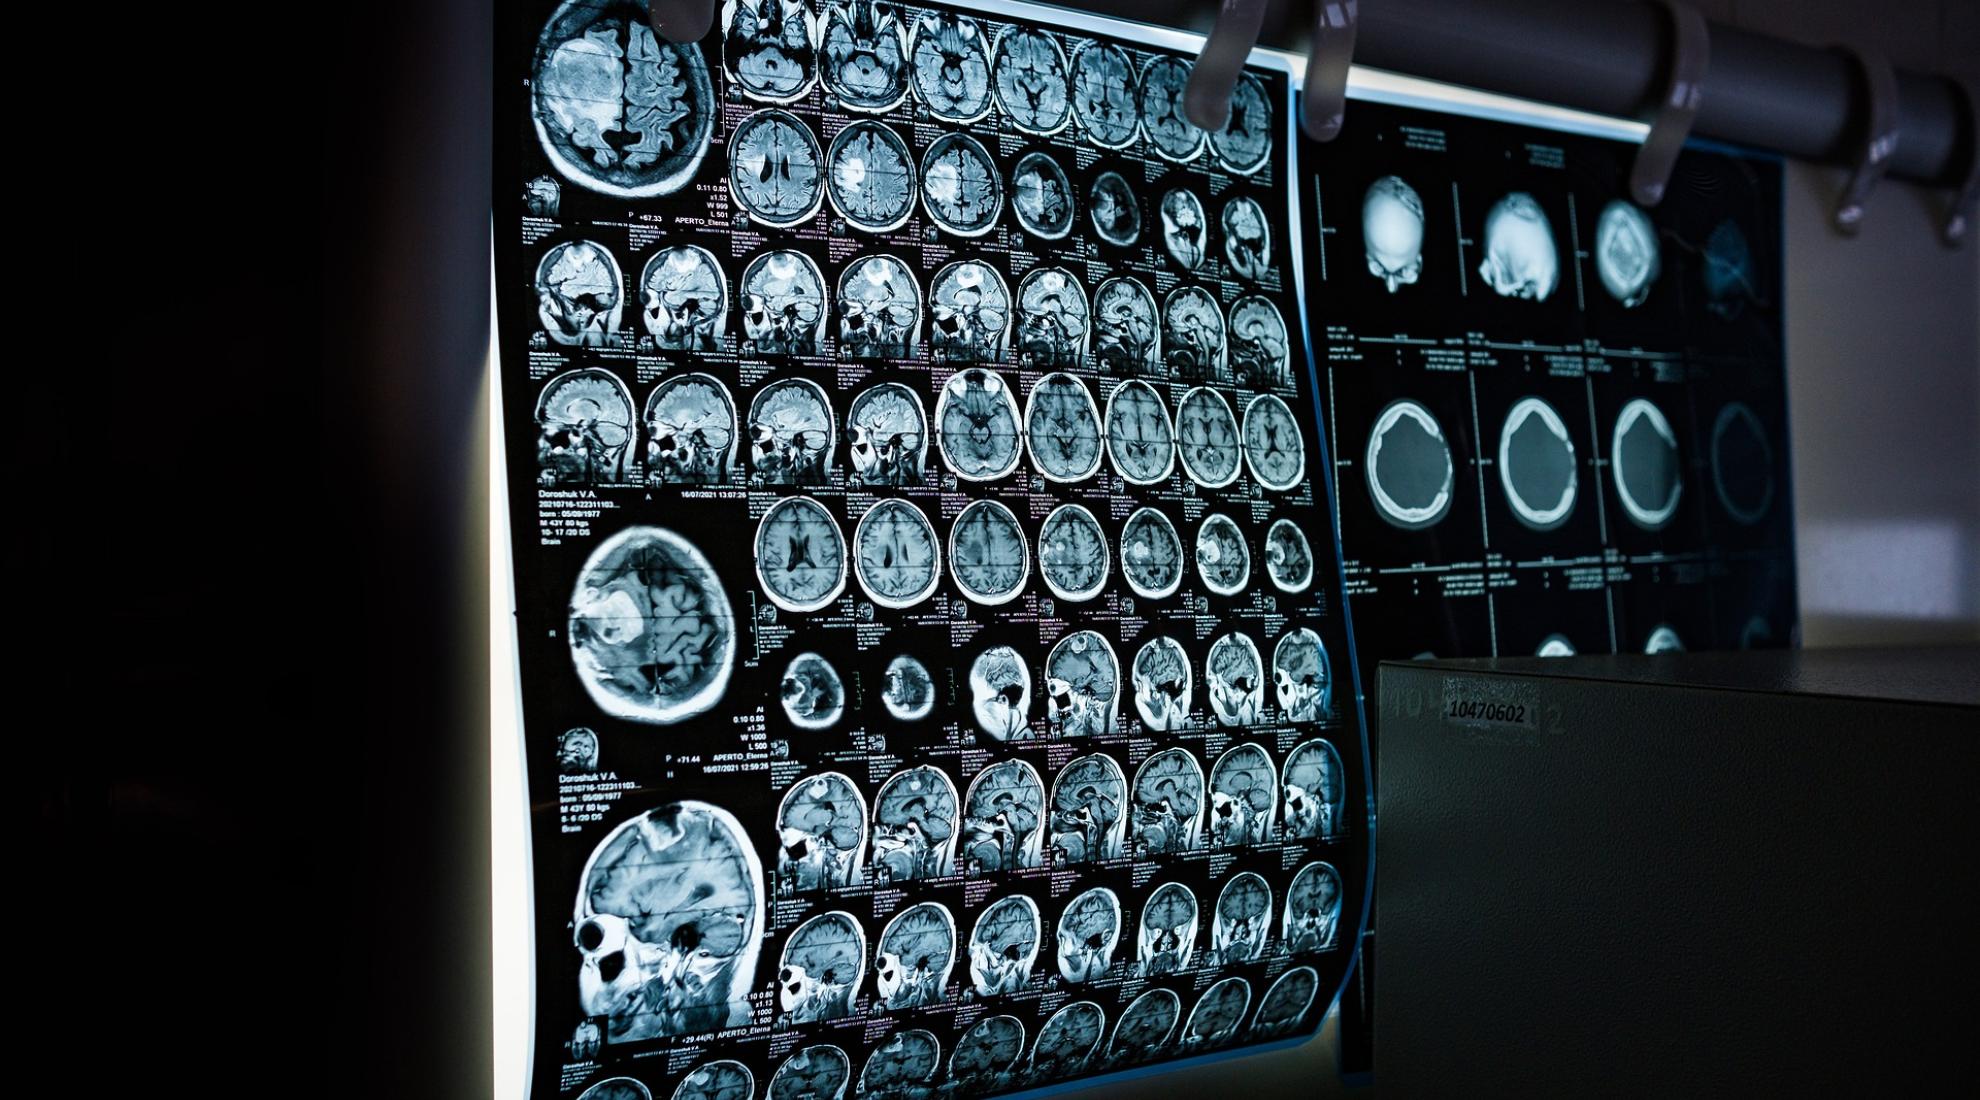

MRI scanning

MRI examinations are vital for survival, but often expensive and only available in larger clinics. A Swiss start-up has developed an ultra-mobile device that could soon be used across the board.

In many cases, MRI sets the gold standard in medical imaging. If a doctor suspects that you’ve had a stroke or developed a tumor, they’ll likely prescribe an MRI. Despite this essential clinical role, it is estimated that 66% of the world’s population do not have access to an MRI scanner, especially due to the high investment costs of a conventional scanner which can amount to USD 1.5 million or more.